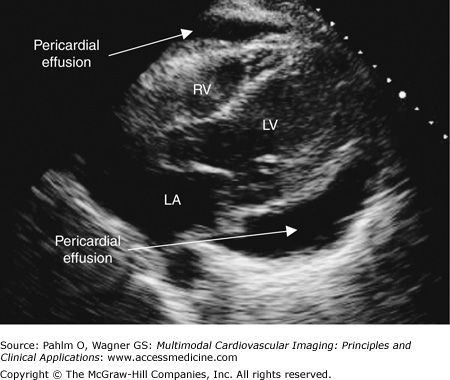

Pericardial Effusion on Transthoracic Echocardiogram

Pericardial effusion. Subxiphoid/subcostal image of a large pericardial effusion, approximately 2.0 cm. LA, left atrium; LV, left ventricle; RV, right ventricle.